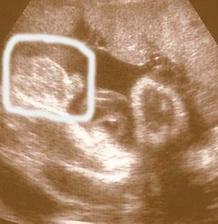

Naše milá rozrůstající se rodinka :o))

Začalo to v dubnu 1999 a zpečetili jsme to nejdříve narozením našeho syna Adámka a poté svatbou 1.10.2005, za chvíli budeme mít první výročí 🙂